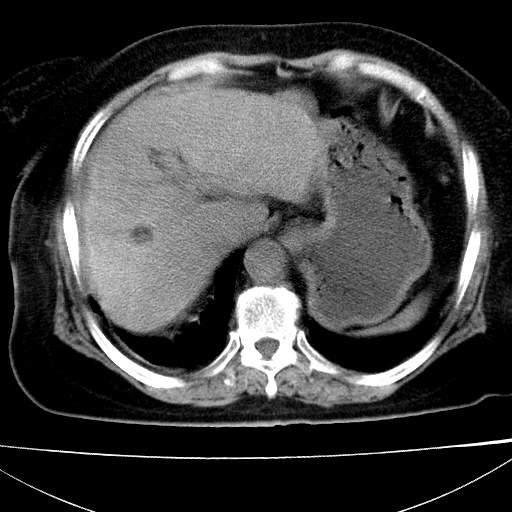

患者女74岁;右上腹胀痛1月,伴恶心,无发热;生活在疫水区。有术后病理及术后半年的追踪ct.

1)慢性血吸虫病(典型)。2)肝硬化。3)肝癌?4)胆囊炎。5)少量腹水。6)右侧少量胸腔积液。

支持.边缘见高密度线条样钙化影.

肝脏体积缩小,肝裂增宽,边缘不平呈波浪状,肝右叶见分隔状条索形钙化,亦见多结节低密度灶,边界不清,肝周可见少许液性暗区,胆囊增大内密度均匀,脾脏下缘低于脏脏的下缘,胸腔亦见液性暗区,余未见明显异常.

诊断:1肝硬化并慢性吸血虫病,脾肿大

2肝内占位,考虑肝癌可能性大,建议做增强

3胆囊炎, 4少量腹水及胸水

胆囊增大饱满,壁增厚。胆囊颈部见软组织密度影。临近肝右叶前段见片状低密度区,病灶下部见条状钙化,少量胸腹腔积液。意见:胆囊颈癌累及肝脏。

病人以胆囊癌手术的,病理结果为中分化腺癌。

现在看看肝右叶内圆形低密度影你们考虑什么呢?

肝内圆形低密度影考虑扩张的胆管

请看3mm重建像如下: